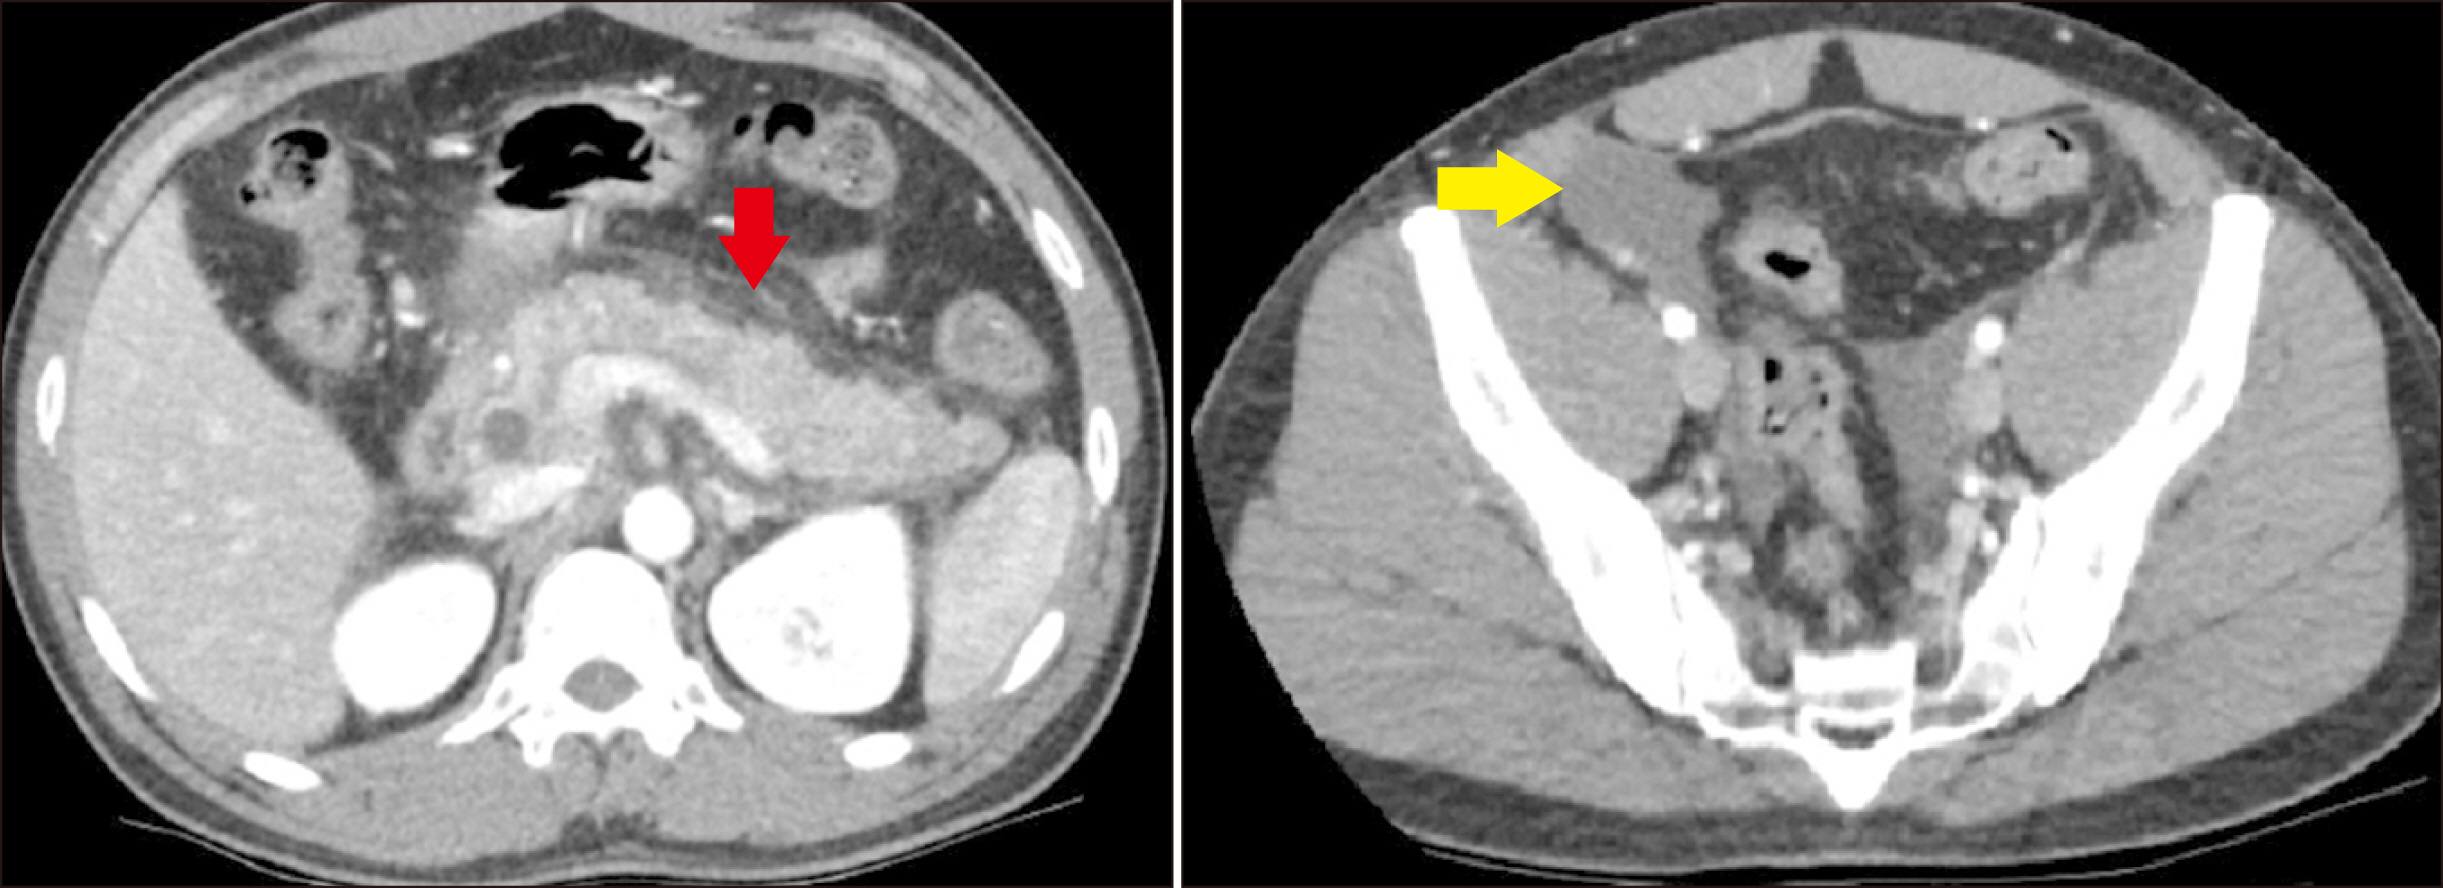

Recurrent pancreatitis in the setting of gallbladder agenesis,ansa pancreatica, Santorinicoele and eventual intraductal papillary mucinous neoplasia (IPMN)

- Gallbladder agenesis is a rare condition. Patients with gallbladder agenesis can present with biliary type symptoms and rarely pancreatitis. We present the case of a 35-year-old gentleman who was admitted and treated for recurrent pancreatitis on a background of gallbladder agenesis, ansa pancreatica and Santorinicoele. He has had several admissions with pancreatitis and has had multiple imaging modalities during these admissions which we delineate. We discuss this rare anatomical variant and describe the course and management of his illness leading up to his eventual diagnosis of intraductal papillary neoplasia (IPMN).